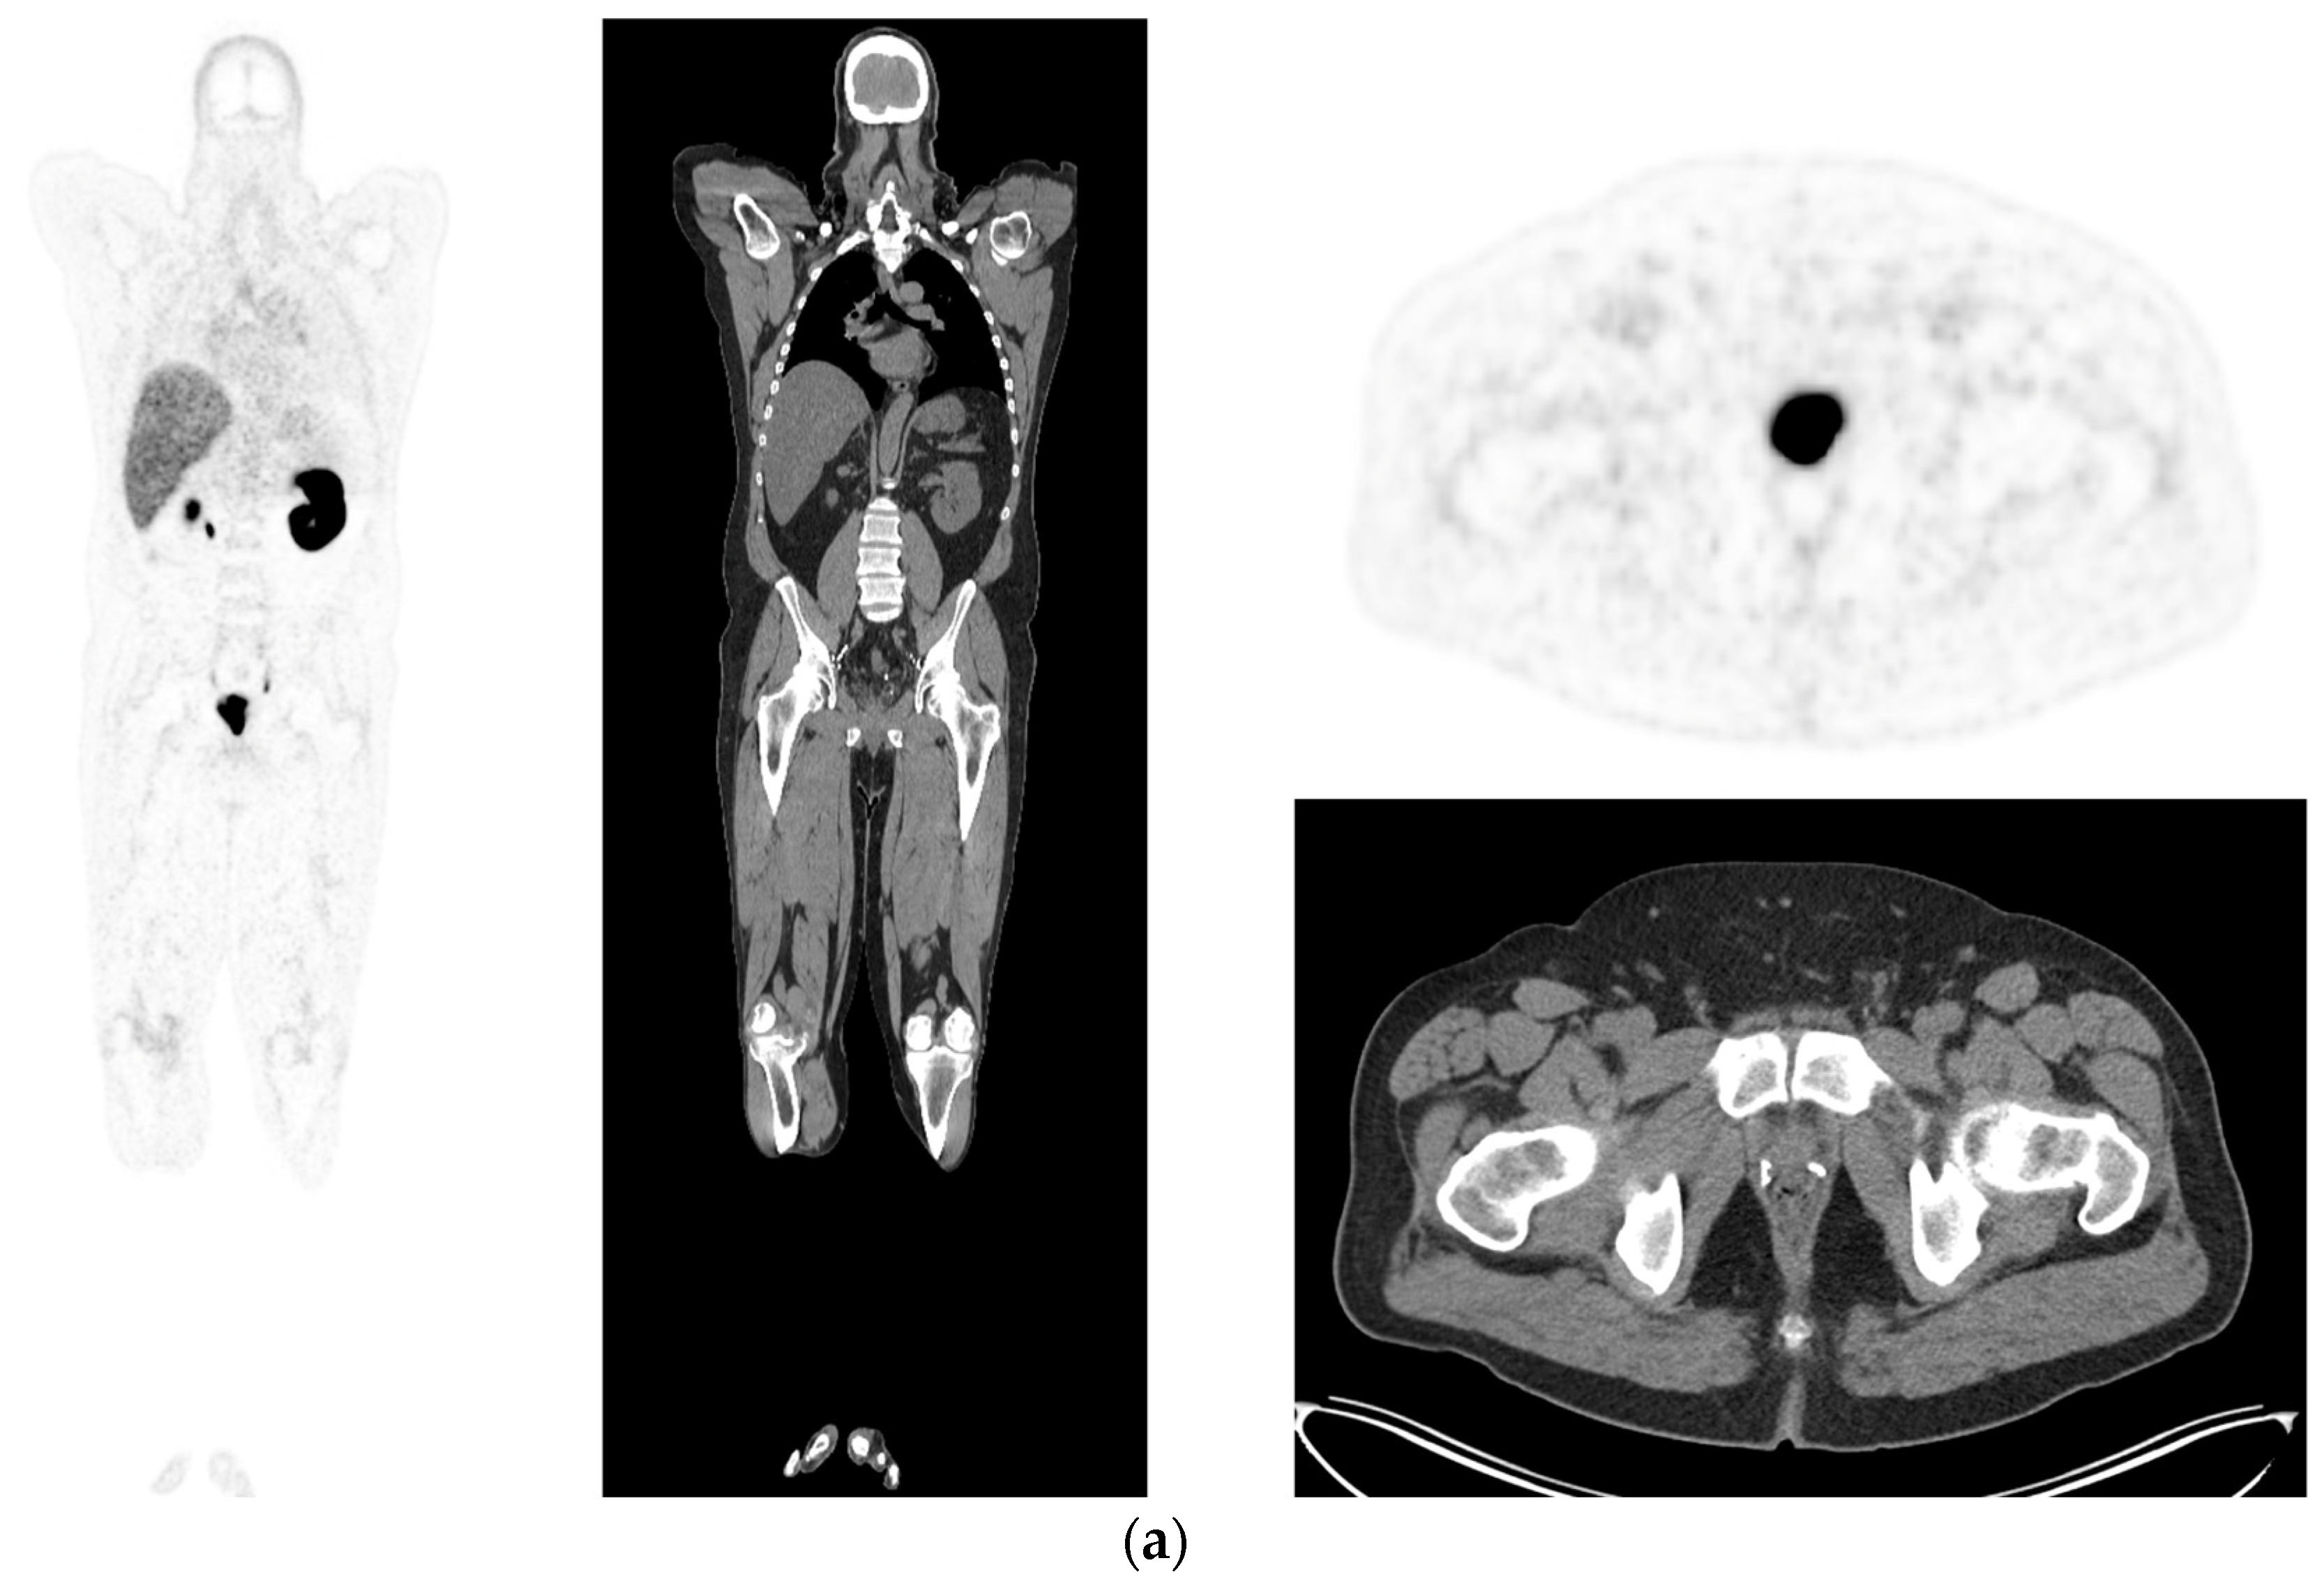

Figure 2.

Primary staging. 70 yr old M; PSA 42; Gleason 4 + 5 = 9; MR scan—PIRADS 6 at right apex; PIRADS 4 at left midzone. PSMA PET-CT: 68Ga-PSMA - 216 MBq; uptake 48 min; BMI = 30.5; Wt 83 Kg. (a): Coronal images—focal uptake midline apex anterior SUV = 26.1 with smaller focus SUV-5.4 right midzone; bulky disease in abdominal nodes; metastasis left humerus; left para-aortic node in thorax; bony metastasis left side of S1. (b,c): enlarged coronal and transaxial images of left common iliac/para-aortic nodal disease and uptake in apex of gland; transaxial images—node measures 14 mm SUV = 40.1; X-hairs show location. (d,e): enlarged coronal and transaxial images of right pelvic nodal that measures 1.4 mm SUV = 5.1; uptake in right midzone and apex as well as disease in left midzone of gland; X-hairs show location. (f,g): enlarged coronal images of para-aortic/para-oesophageal nodal disease in mediastinum; node measures 5.5 mm, SUV = 17.2; X-hairs show location.